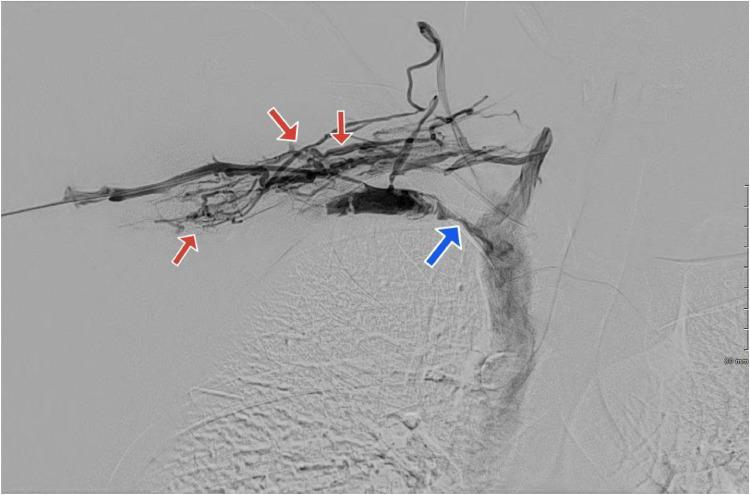

Paget-Schroetter syndrome (PSS), a rare form of deep vein thrombosis affecting the upper extremity, arises from mechanical compression of the subclavian vein at the thoracic outlet. Typically seen in young, active individuals, it manifests with acute onset of arm pain, swelling, and discoloration. Early diagnosis is crucial to prevent chronic complications such as post-thrombotic syndrome, emphasizing the importance of timely intervention and individualized treatment approaches for improved clinical outcomes. We present a case of PSS manifesting in a young adult with no significant medical history.

佩吉特-施罗特综合征(PSS)是一种影响上肢的罕见深部静脉血栓形成形式,由胸廓出口处锁骨下静脉的机械性压迫引起。通常见于年轻、活跃的个体,表现为手臂疼痛、肿胀和变色的急性发作。早期诊断对于预防诸如血栓形成后综合征等慢性并发症至关重要,这强调了及时干预和个体化治疗方法对改善临床结局的重要性。我们报告一例在无重大病史的年轻成年人中表现出的PSS病例。